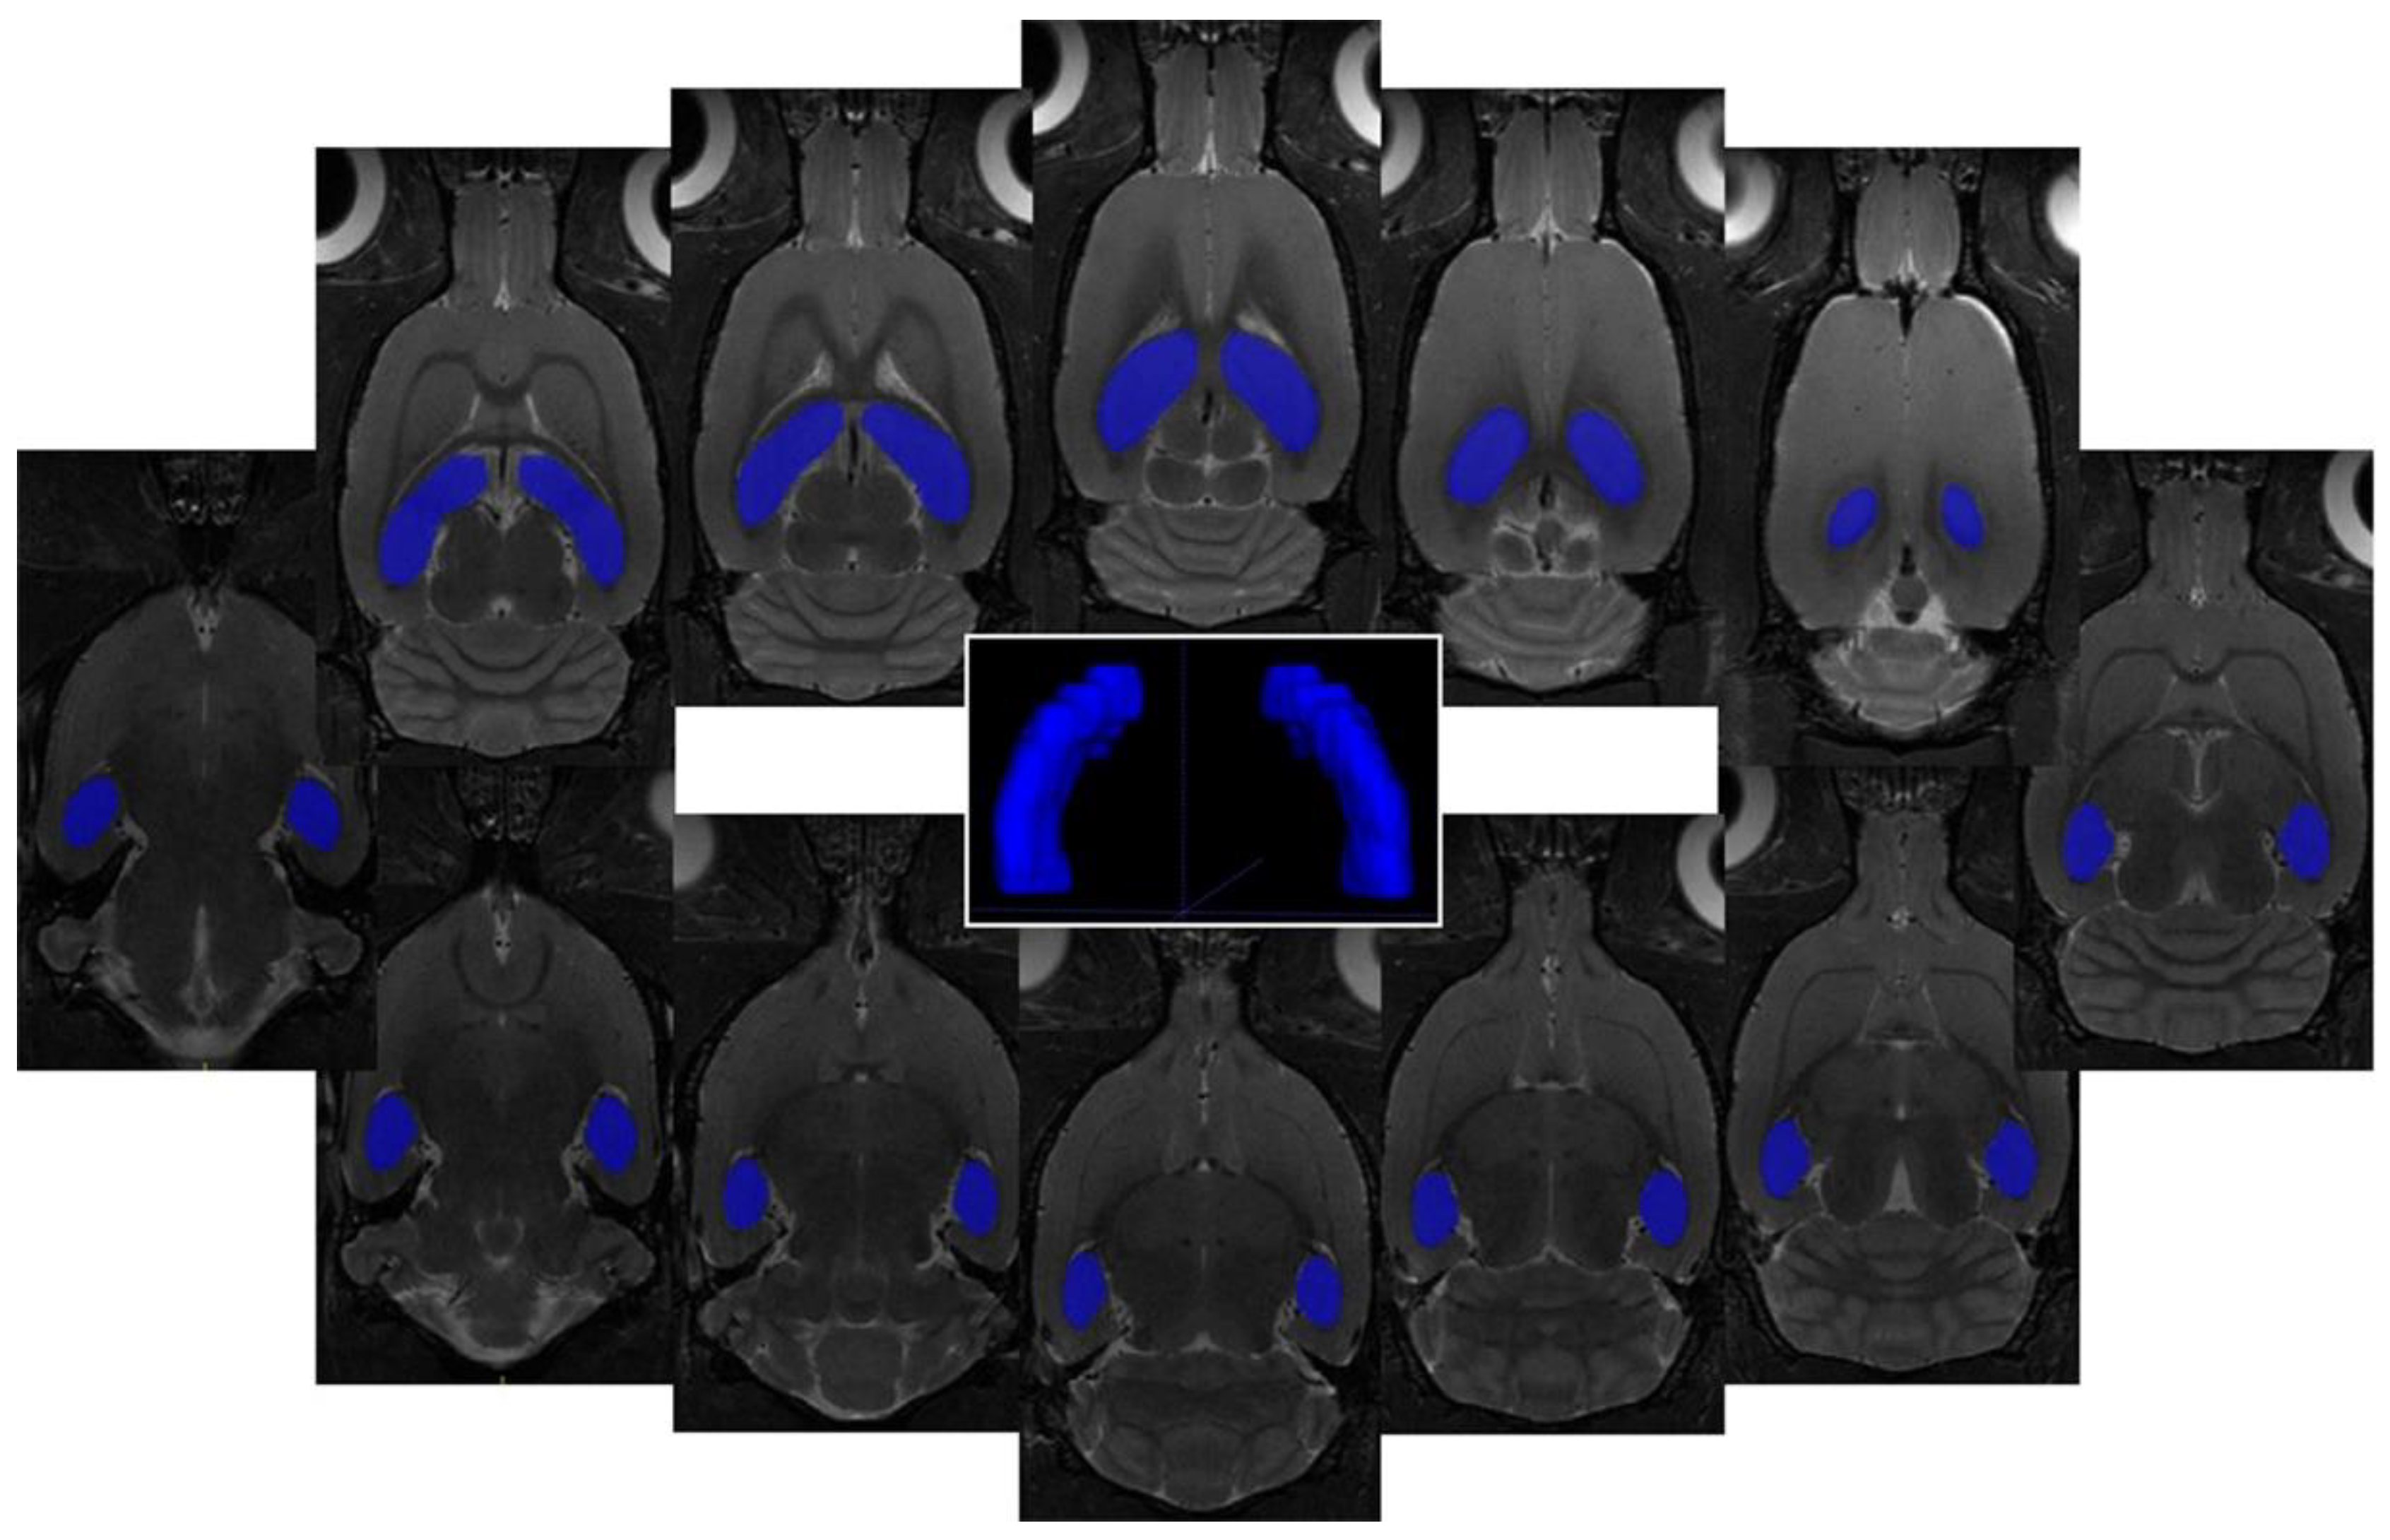

2.7. Image Analysis

3.3. 1H Magnetic Resonance Spectroscopy (MRS) Analysis and Volumetry

4.3. Volumetric Changes in the Brain after Met Diet-Induced hHcy

| Volume Change Mean ± SD | C (Volume Threshold) 91.7 mm3 | Met-C 10 ± 2% | Met-IR-3d 23 ± 6% | Met-IR-7d −6 ± 2% | |

| Tissue Volume Mean ± SD | |||||

| C 96.51 ± 4.78 mm3 | - | independent sample | |||

| Met-C 100.85 ± 1.82 mm3 | 0.031 | - | 2-tailed t-test | ||

| Met-IR-3d 112.81 ± 5.19 mm3 | <0.001 | <0.001 | - | ||

| Met-IR-7d 85.78 ± 2.01 mm3 | 0.001 | <0.001 | <0.001 | - | |